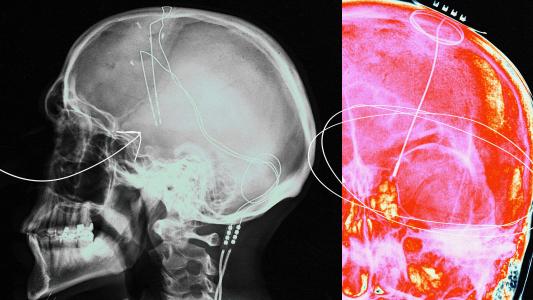

Zapping injured brains can improve cognition and memory

The lasting symptoms of a traumatic brain injury (TBI) can be treated with deep brain stimulation, according to a first-of-its kind trial.